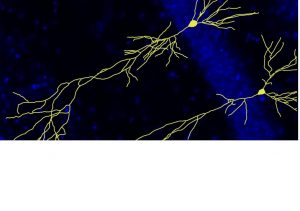

Un estudio de Vithas NeuroRHB ha confirmado que el modelo de terapia multimodal que combina la estimulación transcraneal por corriente directa (tDCS) con realidad virtual muestra beneficios significativos en la rehabilitación de la función motora del miembro superior en pacientes con ictus crónico.

El sistema utilizado por los expertos de neurorrehabilitación para esta investigación es tan completo que incluso detecta la señal cerebral que ocurre en el cerebro cuando la persona lanza la orden a su extremidad de moverse con un fin determinado, según las mismas fuentes que han indicado que gracias a esta tecnología, el sistema "goza de una extraordinaria versatilidad que permite trabajar incluso con pacientes que tienen un difícil acceso a la rehabilitación por la gravedad de sus déficits".

Los resultados confirman que los avances tecnológicos en consonancia con un mayor conocimiento sobre los mecanismos cerebrales implicados en los procesos de recuperación, tras una lesión cerebral, van a suponer una auténtica revolución en la rehabilitación de estos pacientes, ya que permiten incluso mejorías no esperadas en pacientes tradicionalmente considerados como crónicos y con limitadas capacidades de mejoría.